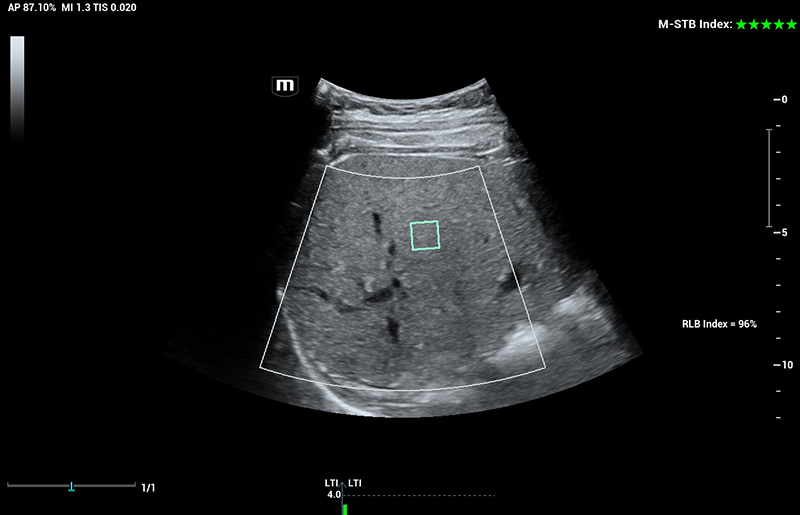

Powered by ZST +

The ZST + platform represents an extraordinary leap forward in ultrasound technology, moving away from traditional beam-forming to channel data processing. This groundbreaking innovation overcomes the traditional trade-offs among spatial resolution, temporal resolution, and tissue uniformity, resulting in unparalleled image quality that empowers infinite imaging solutions.

Resona I9 provides comprehensive clinical solutions for dedicated applications. Based on in-depth insights into different clinical scenarios, it delivers innovations that give users extreme clarity, outstanding intelligence and enhanced diagnostic confidence.